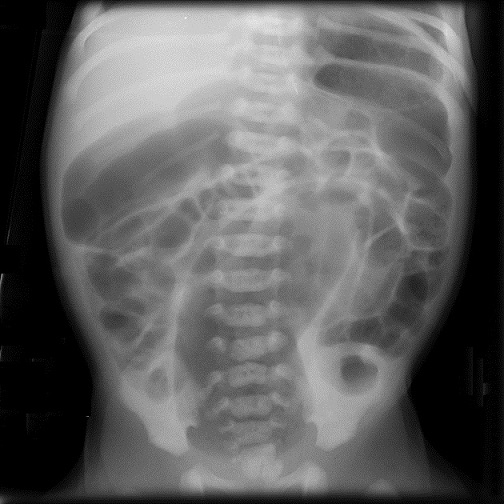

Cliche ASP de face et de profile : Image radiologique

le plus souvent est image de dilatation distendue du colon

avec image de vacuite pelvienne . Dans cas de fistule de

voie urinaire on peut se retrouve de image de la presence de

l'air dans la vessie et tache de calcifie de meconium dans le

colon .

Image radiologique ASP de

face d'une imperfoaration anale cher une nourrison

avec aspect de dilatation gazeuse tres distendue du

colon transverse et colon descendant et de ileon .

Le foie et deux coupole diaprgahmatique sont tres

elevees . Cliche de face ASP , decubitus dorsale |